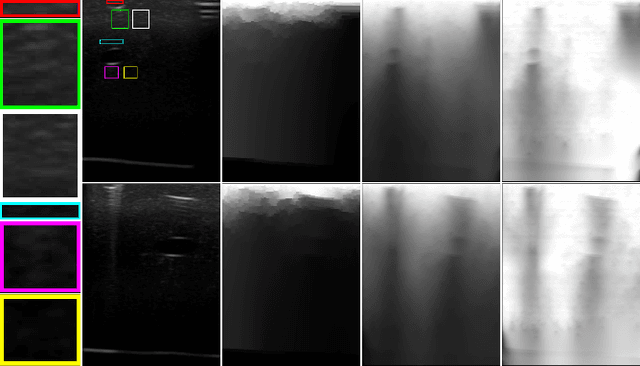

Abstract:Ultrasound 3D compounding is important for volumetric reconstruction, but as of yet there is no consensus on best practices for compounding. Ultrasound images depend on probe direction and the path sound waves pass through, so when multiple intersecting B-scans of the same spot from different perspectives yield different pixel values, there is not a single, ideal representation for compounding (i.e. combining) the overlapping pixel values. Current popular methods inevitably suppress or altogether leave out bright or dark regions that are useful, and potentially introduce new artifacts. In this work, we establish a new algorithm to compound the overlapping pixels from different view points in ultrasound. We uniquely leverage Laplacian and Gaussian Pyramids to preserve the maximum boundary contrast without overemphasizing noise and speckle. We evaluate our algorithm by comparing ours with previous algorithms, and we show that our approach not only preserves both light and dark details, but also somewhat suppresses artifacts, rather than amplifying them.

Abstract:Ultrasound imaging has been improving, but continues to suffer from inherent artifacts that are challenging to model, such as attenuation, shadowing, diffraction, speckle, etc. These artifacts can potentially confuse image analysis algorithms unless an attempt is made to assess the certainty of individual pixel values. Our novel confidence algorithms analyze pixel values using a directed acyclic graph based on acoustic physical properties of ultrasound imaging. We demonstrate unique capabilities of our approach and compare it against previous confidence-measurement algorithms for shadow-detection and image-compounding tasks.